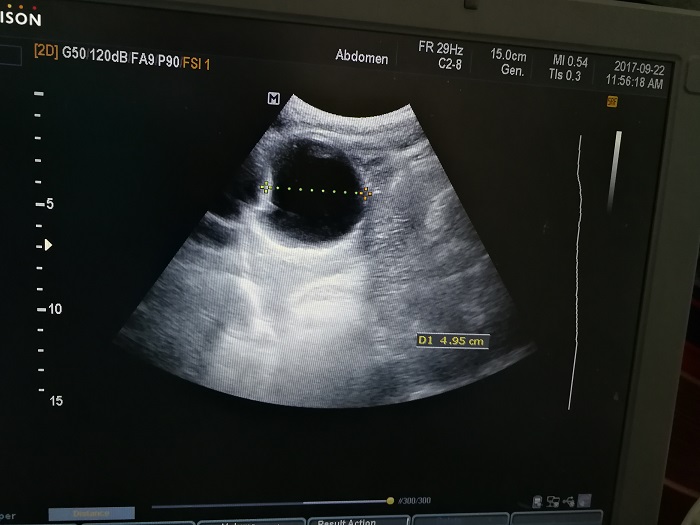

扎西(化名),男,15歲,包蟲病篩查陽性,牧區(qū)孩子,家里有牦牛20頭、羊200只,狗1條,牛羊自家屠宰,飲用河水。

●革吉縣初級中學(xué)篩查點 · B超現(xiàn)場圖片